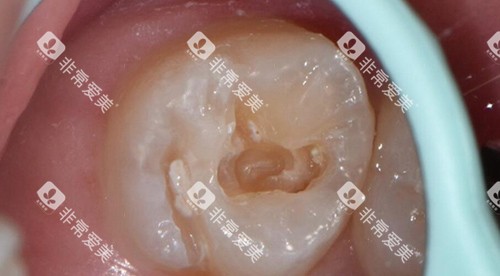

深龋或并发症:

若龋坏深入牙髓引发炎症,需较高行根管治疗(前牙数百元起,后牙可能上千),再行嵌体或牙冠修复,总费用可达数千元。此外,深龋垫底、隔湿等辅助操作可能临时增加100–200元费用。